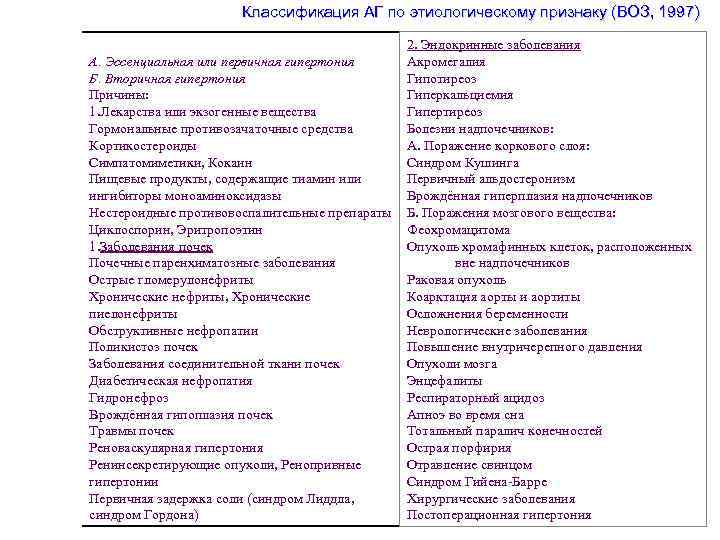

Классификация АГ по этиологическому признаку (ВОЗ, 1997) А. Эссенциальная или первичная гипертония Б. Вторичная гипертония Причины: 1. Лекарства или экзогенные вещества Гормональные противозачаточные средства Кортикостероиды Симпатомиметики, Кокаин Пищевые продукты, содержащие тиамин или ингибиторы моноаминоксидазы Нестероидные противовоспалительные препараты Циклоспорин, Эритропоэтин 1. Заболевания почек Почечные паренхиматозные заболевания Острые гломерулонефриты Хронические нефриты, Хронические пиелонефриты Обструктивные нефропатии Поликистоз почек Заболевания соединительной ткани почек Диабетическая нефропатия Гидронефроз Врождённая гипоплазия почек Травмы почек Реноваскулярная гипертония Ренинсекретирующие опухоли, Ренопривные гипертонии Первичная задержка соли (синдром Лиддла, синдром Гордона) 2. Эндокринные заболевания Акромегалия Гипотиреоз Гиперкальциемия Гипертиреоз Болезни надпочечников: А. Поражение коркового слоя: Синдром Кушинга Первичный альдостеронизм Врождённая гиперплазия надпочечников Б. Поражения мозгового вещества: Феохромацитома Опухоль хромафинных клеток, расположенных вне надпочечников Раковая опухоль Коарктация аорты и аортиты Осложнения беременности Неврологические заболевания Повышение внутричерепного давления Опухоли мозга Энцефалиты Респираторный ацидоз Апноэ во время сна Тотальный паралич конечностей Острая порфирия Отравление свинцом Синдром Гийена-Барре Хирургические заболевания Постоперационная гипертония

Классификация АГ по этиологическому признаку (ВОЗ, 1997) А. Эссенциальная или первичная гипертония Б. Вторичная гипертония Причины: 1. Лекарства или экзогенные вещества Гормональные противозачаточные средства Кортикостероиды Симпатомиметики, Кокаин Пищевые продукты, содержащие тиамин или ингибиторы моноаминоксидазы Нестероидные противовоспалительные препараты Циклоспорин, Эритропоэтин 1. Заболевания почек Почечные паренхиматозные заболевания Острые гломерулонефриты Хронические нефриты, Хронические пиелонефриты Обструктивные нефропатии Поликистоз почек Заболевания соединительной ткани почек Диабетическая нефропатия Гидронефроз Врождённая гипоплазия почек Травмы почек Реноваскулярная гипертония Ренинсекретирующие опухоли, Ренопривные гипертонии Первичная задержка соли (синдром Лиддла, синдром Гордона) 2. Эндокринные заболевания Акромегалия Гипотиреоз Гиперкальциемия Гипертиреоз Болезни надпочечников: А. Поражение коркового слоя: Синдром Кушинга Первичный альдостеронизм Врождённая гиперплазия надпочечников Б. Поражения мозгового вещества: Феохромацитома Опухоль хромафинных клеток, расположенных вне надпочечников Раковая опухоль Коарктация аорты и аортиты Осложнения беременности Неврологические заболевания Повышение внутричерепного давления Опухоли мозга Энцефалиты Респираторный ацидоз Апноэ во время сна Тотальный паралич конечностей Острая порфирия Отравление свинцом Синдром Гийена-Барре Хирургические заболевания Постоперационная гипертония